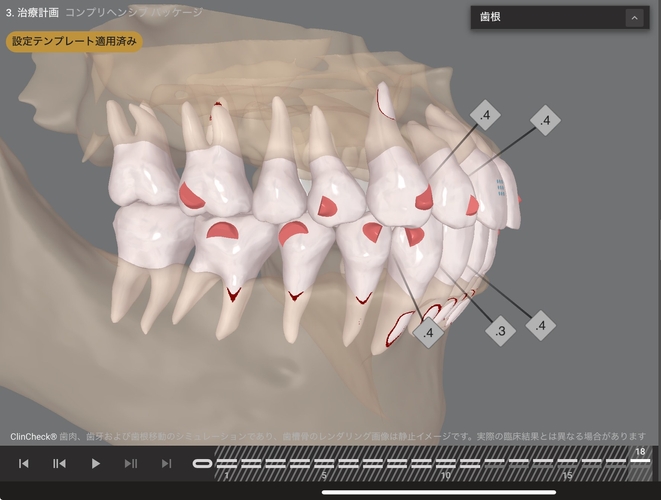

添付のシミュレーション画像(※別の患者の症例)では、右がAIによる自動提案プラン、左が歯科医師の診断を踏まえて調整した治療計画を示している。

画像下に表示されている数字は、使用するマウスピースの枚数を示しており、1枚あたりの装着期間は一般的に約7〜10日とされている。

AIによる提案は治療計画の目安として有効である一方、患者の主訴を丁寧に聞き取り、歯科医師が歯の動きや噛み合わせ、歯根・歯槽骨の状態まで考慮して調整を行うことで、使用するマウスピースの枚数が減り、結果として治療期間が短縮されるケースも見られる。

Drによるプランニングシミュレーション(23 → 18ステージ)